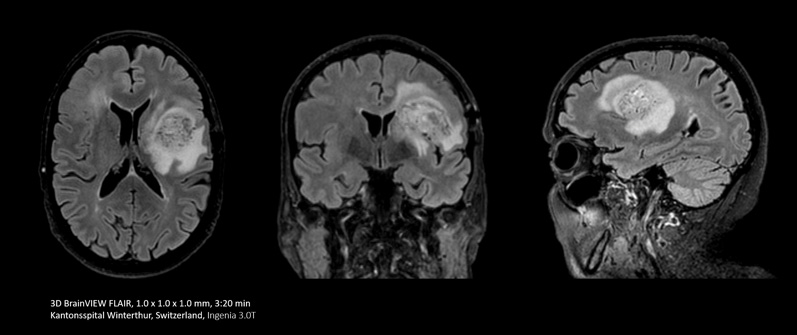

In some cases, like brain and spine examinations, it can be useful to use the power of Compressed SENSE to trade 2D MRI scan sequences for faster 3D sequences. This can allow clinicians to achieve high spatial resolution in tiny nerves and vessels.

With Compressed SENSE you can replace your single orientation 2D FLAIR scan with a multi-orientation 3D volumetric FLAIR scan in only 3 and a half minutes scan time.

I do a lot of brain imaging, and we used to do the FLAIR sequence using a 5 mm thick slice. Now with Compressed SENSE we are able to take a 3D volumetric scan for about 6 minutes down to maybe 3 and a half minutes.”

Dr. Mark Oswood, MD, PhD, Neuroradiologist, Hennepin Healthcare, Minneapolis, USA